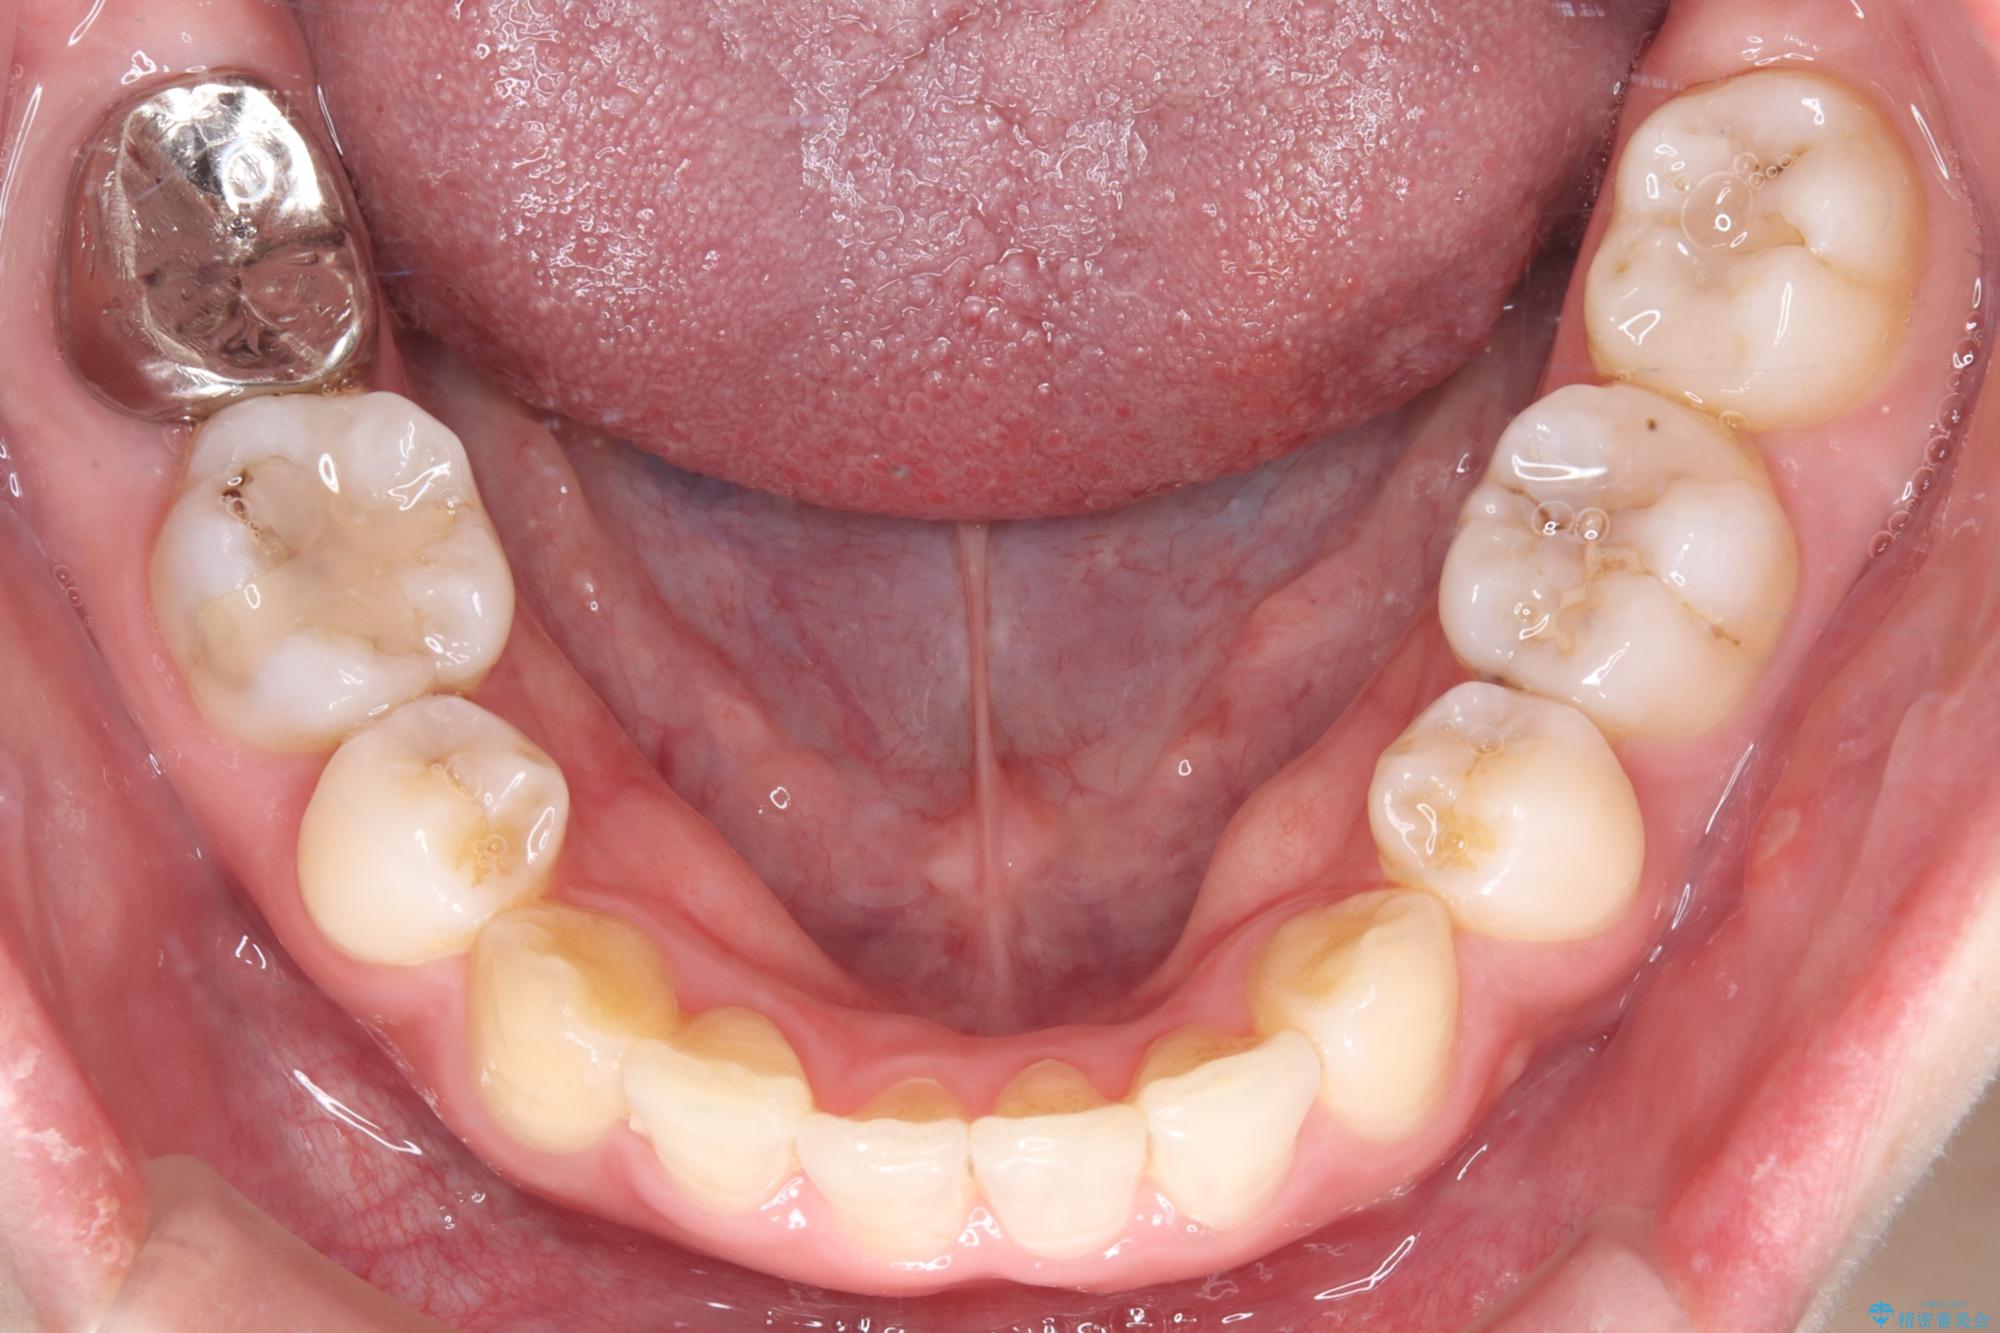

- 前歯から奥歯にかけて歯の重なりが激しい歯のがたつき(重度叢生)を主訴にご来院されました。精密検査の結果、歯が並ぶスペースが大幅に不足しており、歯並びを整え、口元を美しく引っ込めるためには、スペースの確保が必要と診断しました。そこで、上下左右の第一小臼歯(4番目の歯)を計4本抜歯し、そのスペースを利用して歯並び全体を整える抜歯矯正の治療計画を立案。装置には、透明で目立たないインビザラインを採用し、審美性と治療効果の両立を目指しました。

今回の治療では、重度の叢生を改善するため、まず計画通り上下左右4本の小臼歯を抜歯し、歯を並べるための十分なスペースを確保しました。装置には透明で取り外し可能なインビザラインを使用。抜歯によってできたスペースを最大限に活用し、マウスピースを定期的に交換しながら、デコボコを解消しつつ、前歯を効果的に後退させました。

治療の結果、長年の悩みであった重度の歯のがたつきが解消され、口元の突出感も改善。機能的にも安定し、審美的にも美しい、理想的な歯並びを獲得していただけました。